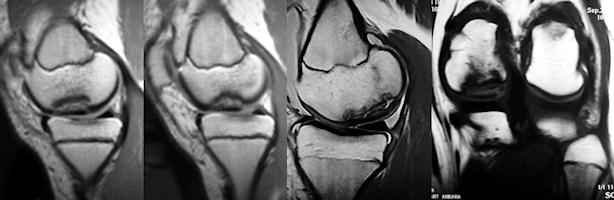

Bu lezyonlar, femur kondilinde görülen aksesuar kemikleşme merkezlerinden ayrılmalıdırlar. OKD diz ekleminde en sık medial femoral kondilin lateralinde, interkondiler çentikte arka çapraz bağın yapışma yeri civarında görülür. Bu bölge klasik yerleşim olarak adlandırılır ve olguların % 50-70’ini oluşturur. Daha nadir olarak lateral femoral kondil ve patella’da yerleşir, tibial plato yerleşimi çok nadiridir. Direkt grafiler lezyonu tanımlamak için yeterli olmakla birlikte, prognoz tayini açısından altın standart manyetik rezonans görüntülemedir. Yakın zamanda tanımlanan MR kriterleri ile lezyonun yatağından ayrılıp ayrılmayacağı büyük oranda tahmin edilebilir. O’Connor ve ark.’a göre, fragman arkasında sıvı varlığını gösteren T-2 ağırlıklı kesitlerde yüksek intensiteli bir hat olması, bu hattın eklem kıkırdağında bir yarık yada defekt ile ilişkili olması ve gadolinyum ile çekilen kontrastlı görüntülerde intensite artışı göstermemesi parçanın yatağından ayrılma eğiliminde olduğunun göstergesidir(O'Connor. J Bone Joint Surg Br. 2002; 84(2):258-62.)